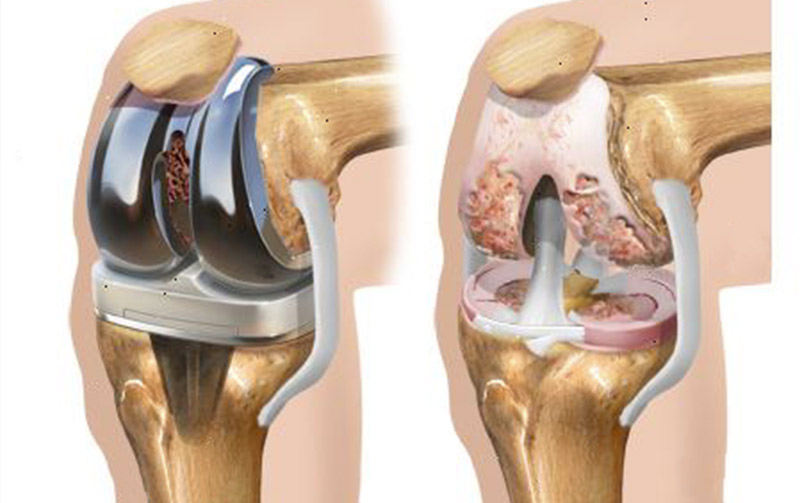

L’artrosi del ginocchio è una malattia che consiste nel consumo delle cartilagini articolari e dell’osso sottostanteche provoca dolore, limitazione funzionale e rigidità articolare. Poiché la cartilagine non si rigenera il danno tende a progredire nel tempo. Le ossa del ginocchio non più protette dalla cartilagine, toccano tra loro, diventano ruvide ed irregolari con conseguente attrito durante i movimenti. Inoltre il sovrappeso o problemi di allineamento del ginocchio (varismo e valgismo) possono aumentare gli stress sull’articolazione ed accelerare il danno. L’artrosi del ginocchio può essere la conseguenza di malattie infiammatorie croniche come l’artrite reumatoide. Altra causa di artrosi di ginocchio possono esseri eventi traumatici come fratture del piatto tibiale che non guariscono in modo adeguato, oppure anche le fratture articolari comunque ben trattate.